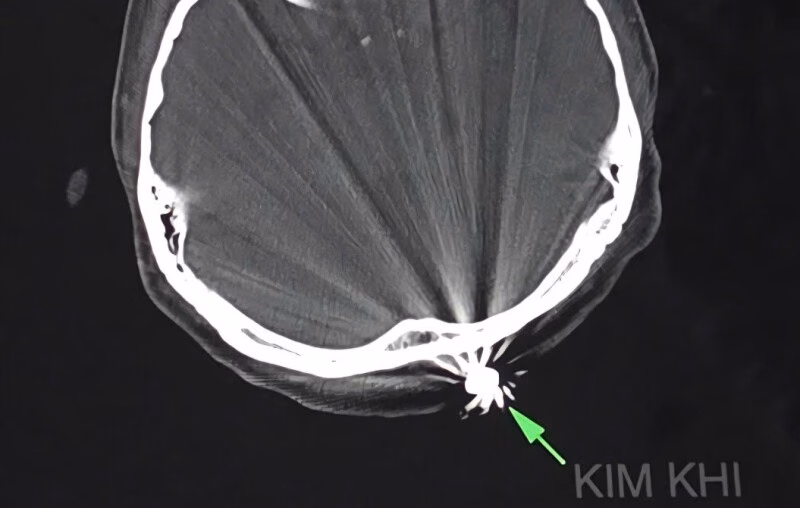

Chị D.T.K.T, ngụ tại TP Cần Thơ, bị trúng đạn khi đang làm vườn tại nhà vào chiều ngày 28/7. Viên đạn đã găm vào vùng chẩm, gây chảy máu nhiều. Bệnh nhân được đưa đến bệnh viện trong tình trạng đau đầu, với vết thương vùng chẩm khoảng 1cm đã cầm máu.

Ngay sau đó, các bác sĩ Khoa ngoại thần kinh đã tiến hành phẫu thuật lấy dị vật và xử trí tổn thương. Quá trình phẫu thuật, bác sĩ đã mở rộng vết mổ khoảng 3cm để lấy ra dị vật kim khí là đầu đạn kích thước 0,5×0,3cm. Ca phẫu thuật diễn ra thuận lợi trong khoảng 45 phút.

Điều đáng chú ý là viên đạn chỉ xuyên qua lớp da, chạm nhẹ vào xương chẩm, không gây tổn thương đến não và cấu trúc lân cận. Hiện, bệnh nhân tỉnh táo, tiếp xúc tốt, vết mổ khô, không ghi nhận triệu chứng thần kinh khu trú.